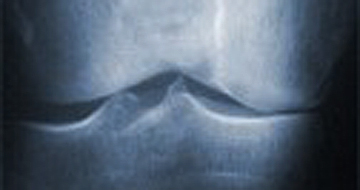

Röntgenaufnahme eines Kniegelenkes mit Arthroseerkrankung

Hier ist der Gelenkspalt auf der Innenseite des Gelenkes aufgebraucht, es ist kein schützender Knorpelbelag mehr vorhanden.